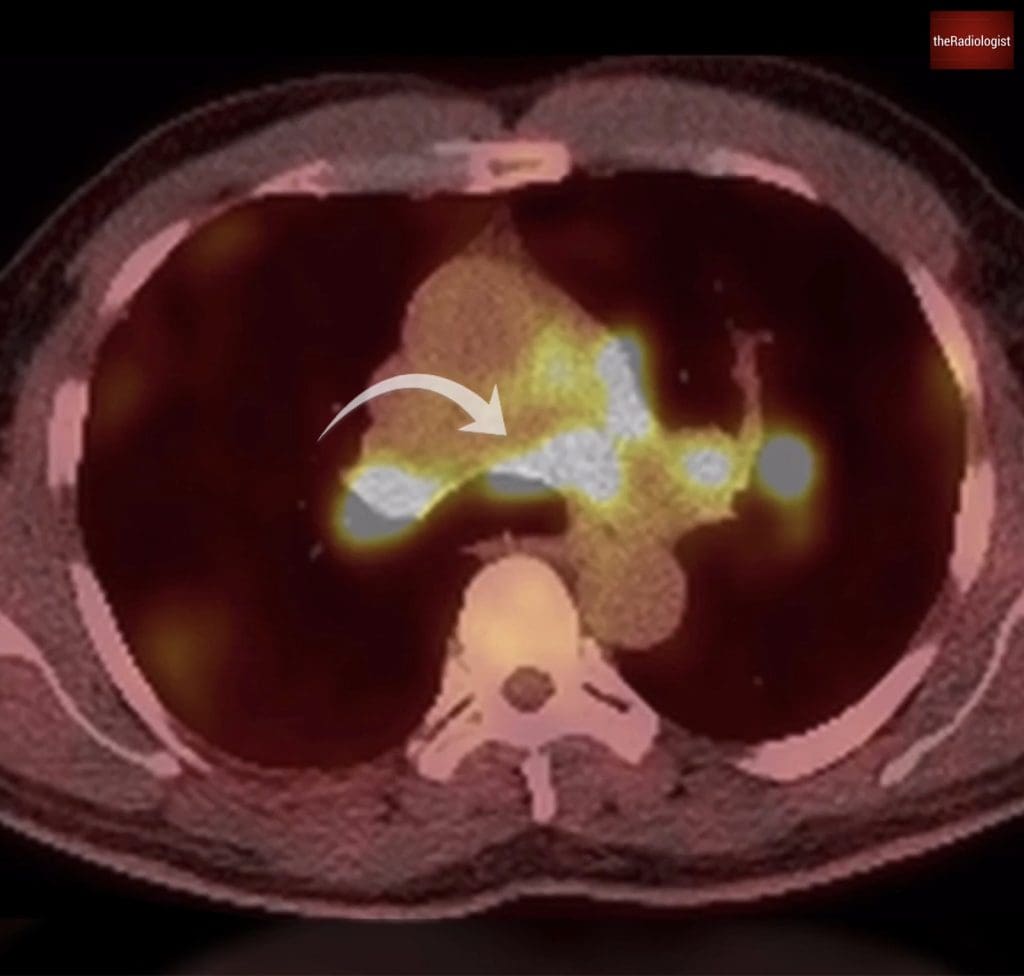

A subsequent PET-CT added a surprising layer: not only were some of the lung nodules FDG-avid, but the pulmonary artery filling defects themselves were also avid, something we wouldn’t expect in typical thromboembolic disease. Normally, thrombus is non-avid on PET imaging.

PET-CT shows interestingly the pulmonary artery filling defects are FDG avid